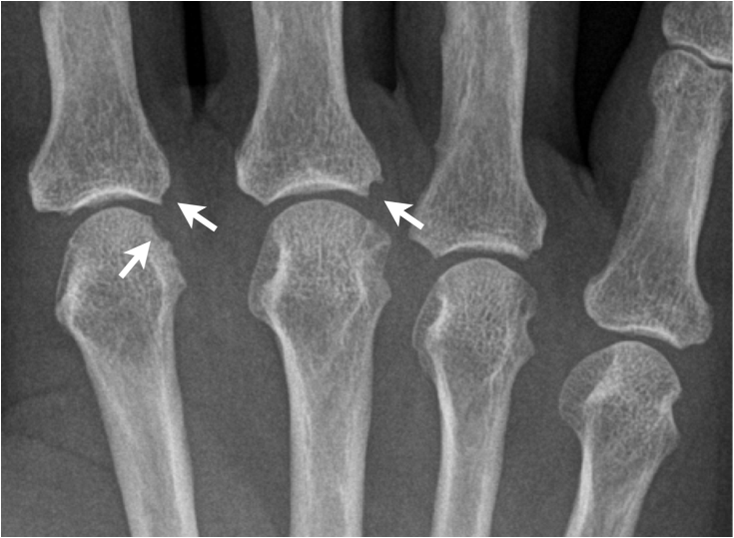

Rheumatoid arthritis may involve any synovial joint. The sacroiliac joints are involved only infrequently. The greatest involvement is in the small joints of the hands, wrists and feet with sparing of the distal interphalangeal joints. In early stages there may be only soft tissue swelling and juxta-articular osteoporosis. Next joint space narrowing and early erosive changes are seen.

In general, the presence of erosions bespeaks some type of inflammatory disease, whether the erosions are due to synovial hypertrophy, crystalline deposits, or infection. In rheumatoid arthritis, the erosions follow the development of an inflammatory proliferation of the synovium, called pannus. As this pannus increases in amount, it begins to cause erosions of the chondral surface. As the pannus increases further in amount, one begins to see erosions at the periarticular "bare" areas. These "bare" areas refer to bone within the synovial space which is not covered by articular cartilage. The articular cartilage tends to protect the bone that it covers. The marginal "bare" areas are not covered by cartilage, and the earliest erosions of rheumatoid arthritis are seen here.

Fig. 15. Rheumatoid arthritis. A) Early erosive changes are seen at the bare areas of the second and thirs metacarpal-pahalangeal joint. B.) In a patient with long standing rheumatoid arthritis marked destruction of carpal bones and styloid process has occurred. Note luxation of the first MCP joint, erosions at the other MCP joints and generalized osteoporosis.